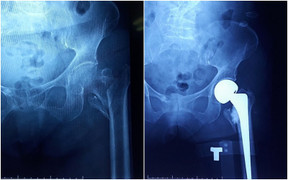

Bệnh viện Đa khoa tỉnh Quảng Ninh tiến hành mổ thay khớp háng nhân tạo cho cụ bà 102 tuổi, đây là bệnh nhân cao tuổi nhất từ trước đến nay được các bác sĩ bệnh viện thực hiện phẫu thuật thành công.